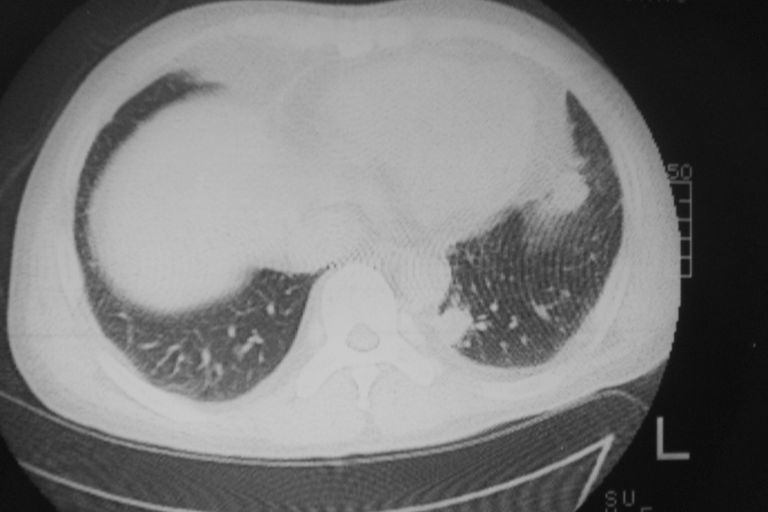

标题: CT10574:男 50岁胸部CT请会诊!

患者 男 50岁 无痛性咯血3天,无其他不适.

左下肺结节状软组织密度影,边缘有毛刺,考虑周围型肺癌。

1 左肺下叶基底段见两结节软组织密度灶, 肺窗边缘见有毛刺征像, 不能排除占位. 2 建议结合临床治疗一周后ct随访在看其结果.

临近胸膜增厚,病变周围肺不清,稍有分叶。结节密度略高,肺、纵隔窗差异不大,肺癌待排。前方还有一个

左下肺结节状软组织密度影,一个边缘有卫星病灶,邻近胸膜增厚.另一个有毛刺.心影周围水样密度影环绕.考虑:

1.肺癌可能.肺tb待排.

2.左侧胸膜增厚.心包积液.